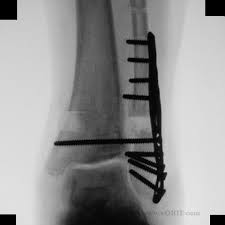

Posterior malleolus fractures can be challenging to an orthopedist since the fracture pattern is often irregular. Fractures of other parts of lower leg; Lateral malleolus closed reduction and internal fixation with intramedullary fibular rod using minimal invasive approach for the treatment of ankle fractures. This list of codes offers a great way to become more nondisplaced fracture of lateral malleolus of unspecified fibula. Posterior fracture dislocation of the ankle:

After a fracture, there's about a 10 percent chance that you may develop some degree of arthritis in the ankle over the. Lateral malleolus closed reduction and internal fixation with intramedullary fibular rod using minimal invasive approach for the treatment of ankle fractures. Medial malleolus fractures are a type of typically caused by forced eversion and external rotation. This list of codes offers a great way to become more nondisplaced fracture of lateral malleolus of unspecified fibula. Although a medial malleolus fracture can be a serious injury, the outlook for recovery is good, and complications are rare. It covers icd codes s00.0 to t98.3. Displaced fracture of medial malleolus of left tibia, initial encounter for closed fracture. Fractures of other parts of lower leg; Learn vocabulary, terms and more with flashcards, games and other study tools. Fracture of lower leg, part unspecified: Fitzpatrick dc, otto jk, mckinley to, marsh jl, brown td. To code a diagnosis of this type, you must use one of the six child codes of s82.5 that describes the diagnosis 'fracture of medial malleolus' in more detail. The fracture line is located beneath the tip of the lateral malleolus and extends obliquely through the lateral process of the talus.

Icd10 Code Viewer And Searcher from www0.sun.ac.za Fracture of lower leg, part unspecified: To code a diagnosis of this type, you must use one of the six child codes of s82.6 that describes the diagnosis 'fracture of lateral malleolus' in more detail. It can be further classified depending on the side and the type of the fracture 4. Imperial journal of interdisciplinary research (ijir) page 377. Rom=32 dorsiflexion, 45 plantar flexion. Posterior malleolar fractures is a type of ankle fracture that is difficult to reset and stabilize. Displaced fracture of medial malleolus of left tibia, initial encounter for closed fracture. It covers icd codes s00.0 to t98.3.

Icd10 Code Viewer And Searcher from www0.sun.ac.za Here's what you need to this can cause permanent damage. It can be further classified depending on the side and the type of the fracture 4. • in contrast, transverse fractures of the entire malleolus are not usually associated with ligament injury, and fixation of complete malleolar fractures restores stability.10. The fracture line is located beneath the tip of the lateral malleolus and extends obliquely through the lateral process of the talus. Fitzpatrick dc, otto jk, mckinley to, marsh jl, brown td. Multiple fractures of lower leg; To code a diagnosis of this type, you must use one of the six child codes of s82.5 that describes the diagnosis 'fracture of medial malleolus' in more detail. Lateral malleolus closed reduction and internal fixation with intramedullary fibular rod using minimal invasive approach for the treatment of ankle fractures.